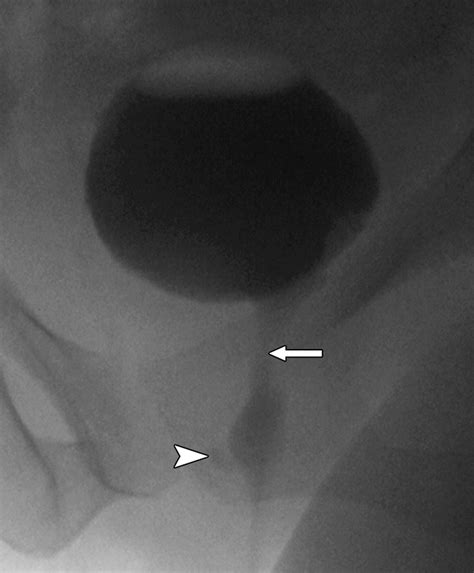

Voiding Cystourethrogram (VCUG) Uses contrast dye to see if the pouch fills during urination.

Diagnostic Procedures

Diagnosis requires a high index of suspicion, especially when standard treatments for UTIs fail. A physician will typically perform a physical exam, which may reveal a tender mass along the anterior vaginal wall. If pressure is applied to the mass, it is not uncommon for a small amount of urine or purulent discharge to exit the urethra.